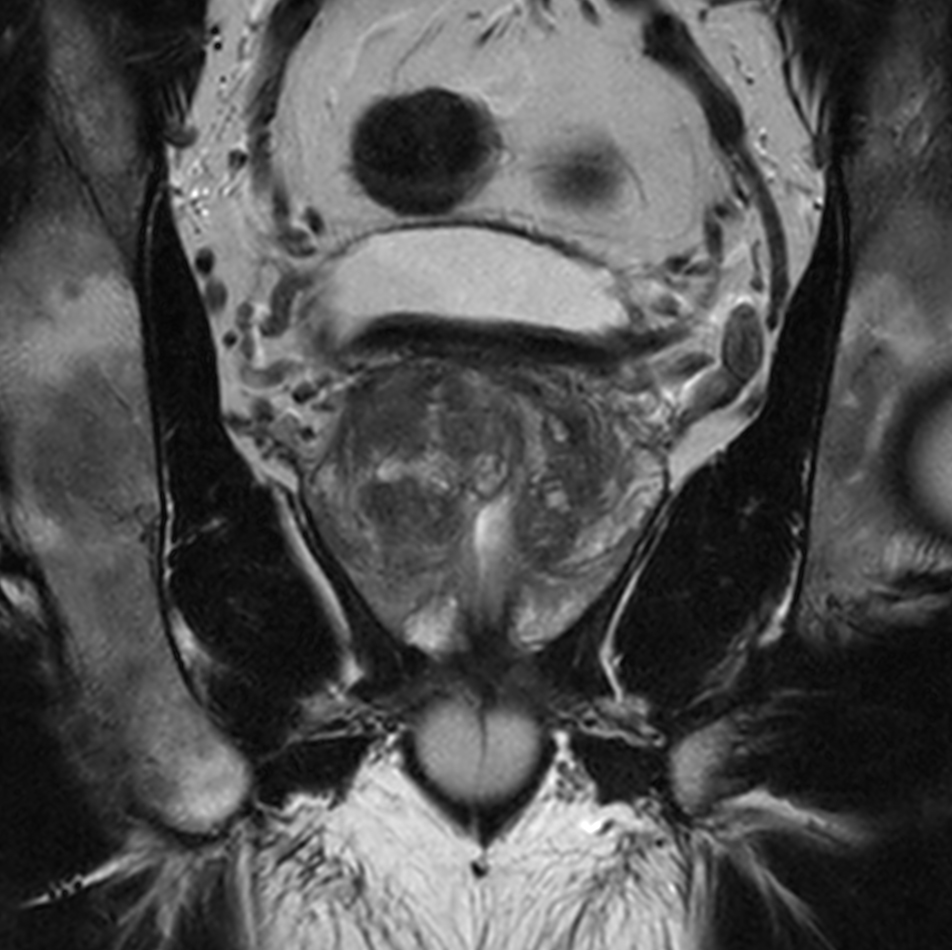

Coronal T2w TSE with Compressed SENSE